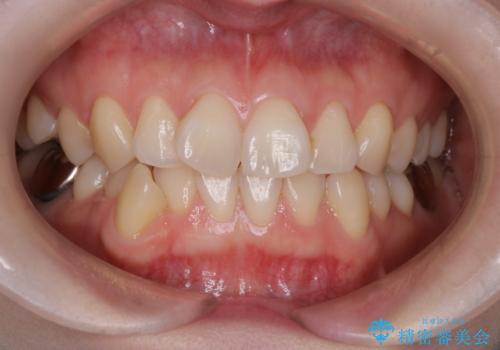

- 前歯の翼状捻転の改善を希望してこられた患者様です。

下顎の叢生はインビザラインで解決することがきましたが、上顎の捻転が完全には改善できなかったため、上顎は途中からワイヤーを用いて治療を行っています。